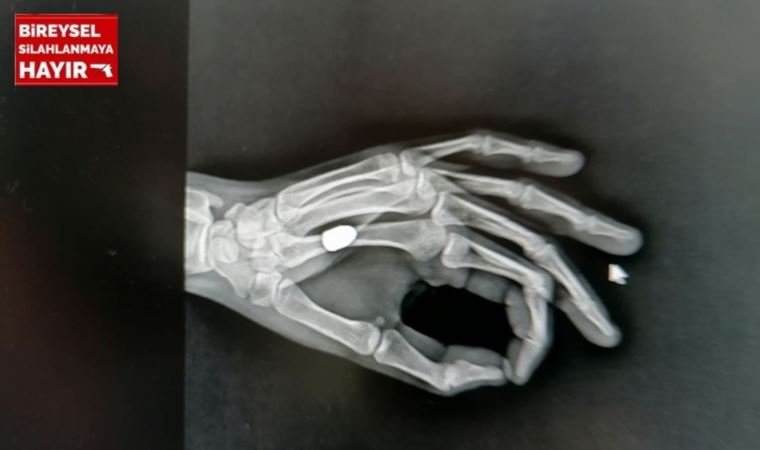

Özellikle Trabzonspor’un geçen sezon şampiyonluğu ve sonrasında alınan güvenlik önlemleri ile olumlu sonuç veren ‘Mutluluğa kurşun sıkmayın’ kampanyasından yaklaşık 5 ay sonra kentte ilk kez yorgun mermi vakası yaşandı. Sürmene ilçesi Çarşı Mahallesi’nde 22 Ağustos’ta otobüs durağında beklediği sırada elinde aniden acı hisseden Mehmet İskender, sol avucunun kanadığını fark etti. Kanı arkadaşının yardımıyla temizleyen İskender, Sürmene Devlet Hastanesi’ne gitti. Tedaviye alınan İskender’e çekilen röntgende, avucuna yorgun merminin saplandığı tespit edildi. Mermi çekirdeği elinden ameliyatla alınan İskender, taburcu edildi. Polis ekipleri, olayla ilgili inceleme başlattı.

Sürmene Devlet Hastanesi Başhekimi Osman Yoloğlu, röntgen filminde mermi tespit ettiklerini belirterek, “Elinde ağrı hissettiğini söyleyen hastamızın elinde de bir yarası vardı. Yaptığımız tetkikler sonrası elinde, mermi çekirdeği olduğunu tespit ettik. Hastamızı hemen ameliyata aldık ve elinden mermi çekirdeğini çıkarttık. Durumu, çok şükür iyi” diye konuştu.